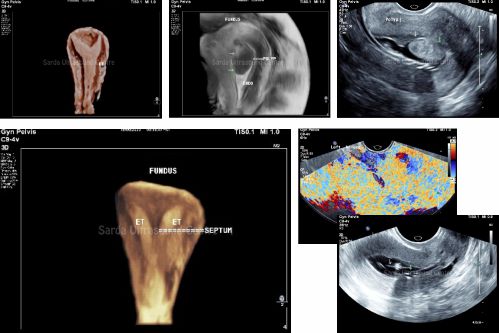

4D volume probes for Transvaginal ultrasound provide high resolution crisp imaging for detailed evaluation of uterine anomalies or masses, adnexae and ovaries.

3D imaging when combined with Sonohysterosalphingography can provide further details of uterine cavity (Polyp, adhesions, endometrial lining, etc) and Patency of fallopian tubes in cases of infertility and AUB.